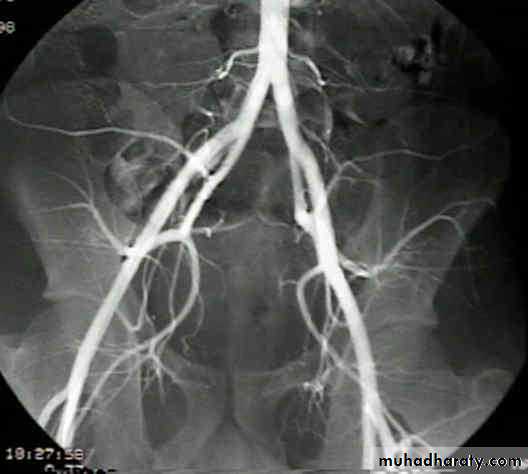

Angiography of iliac vessels